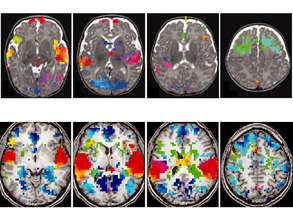

Pictures in Mind

Your Mind's Eye